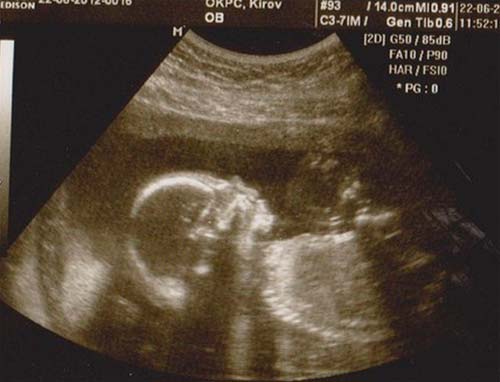

Si vous n'avez pas subi d'échographie au cours du deuxième trimestre, il sera nommé. Un médecin spécialiste vérifiera les principales dimensions du corps et des membres du fœtus, l'état des organes internes et un certain nombre d'autres indicateurs. Le placenta ne sera pas moins examiné en profondeur.

Photo échographique à 21 semaines (cliquez pour agrandir):

Avec un emplacement réussi du fœtus, vous pouvez découvrir le sexe du bébé. Mais le futur garçon ou fille peut parfois «se cacher» jusqu'à la naissance même.